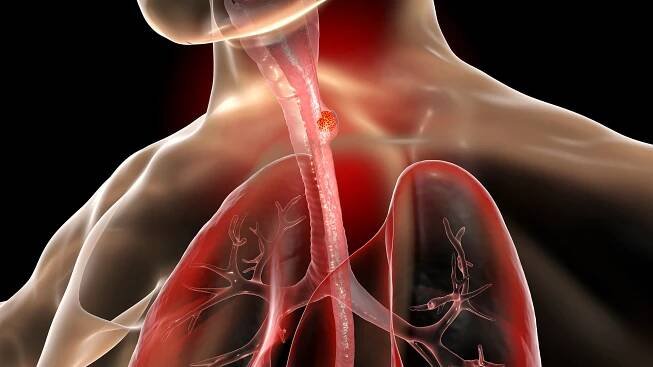

Jako nádory jícnu označujeme maligní onemocnění vznikající maligním zvratem dlaždicového epitelu jícnu (epidermioidní karcinom) nebo epitelu Barretova jícnu či mucinosních žláz stěny jícnu (adenokarcinom).

Jícen tvoří začátek zažívacího traktu. Skládá se z několika typů buněk, které se mohou...